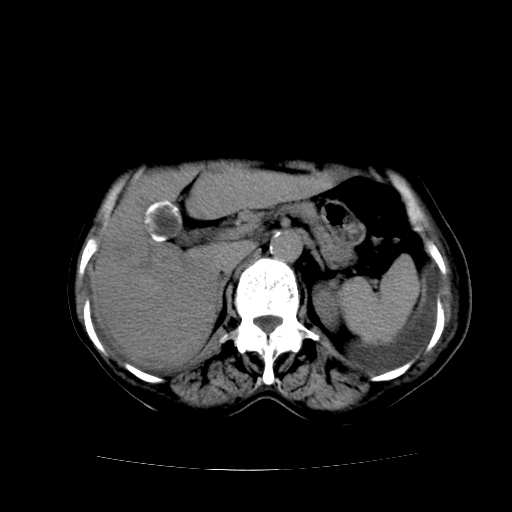

癌性淋巴管炎,肝脏转移,瓷胆囊

1)左侧乳腺癌并左侧腋窝及纵隔淋巴结转移,两肺淋巴道转移(癌性淋巴管炎),肝脏多发性转移。2)双侧胸腔积液。3)慢性胆囊炎。

5、肝转移瘤;

6、瓷胆囊。

1)左侧乳腺癌并左侧腋窝及纵隔淋巴结转移,肝脏多发性转移。2)双侧胸腔积液伴双肺蝶翼样磨玻璃高密度影,双侧肺门血管影增粗(图像不全,肺门层面没纵隔窗),考虑心功能不全所致。3)慢性胆囊炎伴壁钙化。

左侧乳腺癌并左侧腋窝及纵隔淋巴结转移,两肺淋巴道转移(癌性淋巴管炎),肝脏多发性转移。2)双侧胸腔积液。3)瓷胆囊